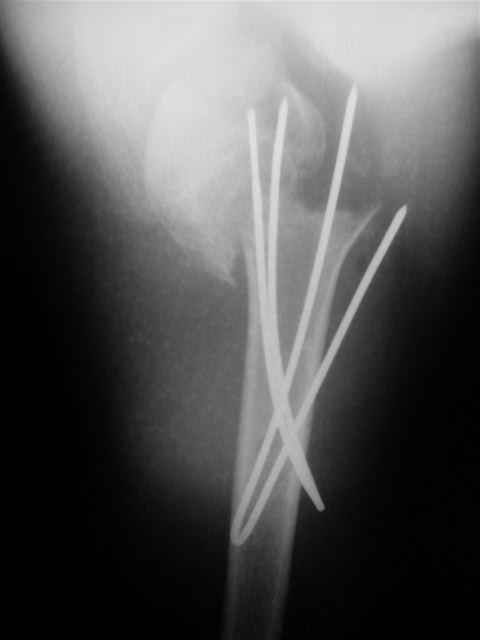

Коллеги, Больной прооперирован вчера. 19 летний пациент с переломом шейки плеча. Закрытая репозиция и чрескожная фиксация спицами под контролем ЭОПа ( техника проф. Лазарева)

Интраоперационный контроль на стабильность фиксации - сомнений в стабильности фиксации не возникло. Послеоперационный контроль сегодня......

Необходимость послеоперационного Рг контроля..... Больной запланирован на повторную манипуляцию и транспозицию спиц Евгений И Чекашкин